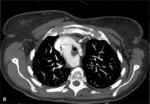

RYCINA. Badanie wykonane 64-rzędowym tomografem komputerowym jednolampowym. Akcja serca podczas badania – 87 uderzeń/min.

Zakres badania – cała klatka piersiowa. [A] Rekonstrukcja VR uwidoczniła prawostronny łuk aorty. [B] Warstwa poprzeczna na poziomie łuku aorty. Widoczne są: niepełny pierścień naczyniowy otaczający tchawicę i przełyk utworzony przez łuk aorty i tętnicę podobojczykową lewą otaczającą tchawicę i przełyk (strzałki). Ściana tętnicy podobojczykowej zawiera blaszki miażdżycowe zwężające jej światło 40%. [C] Warstwa poprzeczna na poziomie nadnercza lewego – widoczny guzek nadnercza lewego (strzałka). [D] Rekonstrukcja VR uwidoczniła prawostronny łuk aorty z częściowym pierścieniem naczyniowym.

- zwężenie 40% tętnicy podobojczykowej lewej w odcinku proksymalnym za jej odejściem od łuku aorty; tętnica otaczająca tchawicę wzdłuż jej przedniej ściany tworzyła wraz z prawostronnym łukiem aorty niepełny „pierścień” (rycina B),